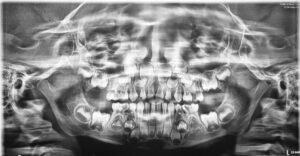

With “CARESTREAM CS-9600” the OPG image quality is one of the finest where almost all details of anatomical region, in any age group can be interpreted to perfection.

PANORAMIC IMAGES IN DIFFERENT AGE GROUPS 👇🏻